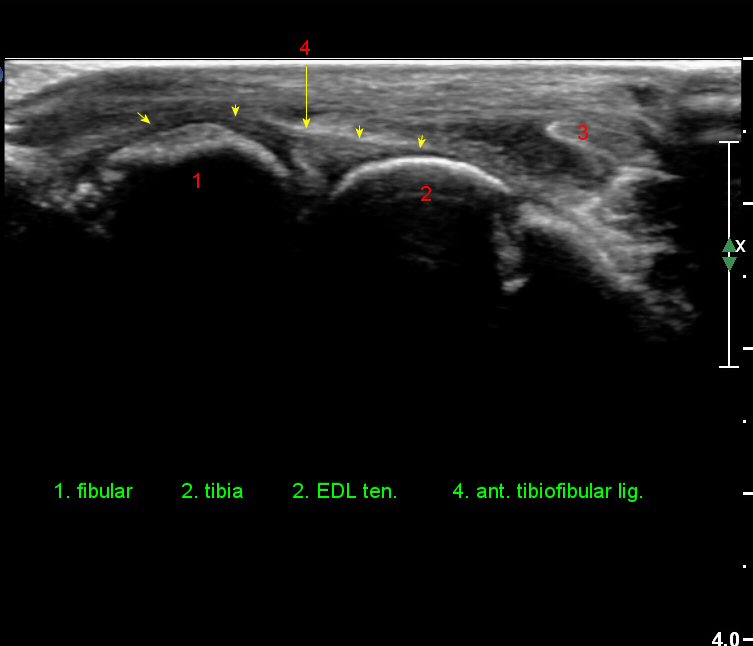

Àü°ÅºñÀδë Á¾´Ü¸é°Ë»ç¿¡¼­ ¾È´ë ºñ°ñ ºÎÂøºÎÀÇ Àú¿¡ÄÚ ºÎÁ¾°ú ºÎºÐÆÄ¿­ÀÌ °üÂûµÈ´Ù(»çÁø 4).

Àü°ÅºñÀδë Á¾´Ü¸é°Ë»ç¿¡¼­  Àú¿¡ÄÚ ºÎÁ¾ÀÌ °¨¼ÒÇϰí ÀδëÀÇ ¿¡ÄÚ°¡ Áõ°¡µÇ¾ú´Ù(»çÁø 2, 3, 4).

Àü°ÅºñÀδë Ⱦ´Ü¸é°Ë»ç¿¡¼­ Àü°Åºñ ÀÎ´ë ¾ÕÂÊ ºÎÀ§ÀÇ °æ¹ÌÇÑ Àú¿¡ÄÚ ºÎÁ¾ÀÌ °üÂûµµ´Ï´Ù(»çÁø 5).